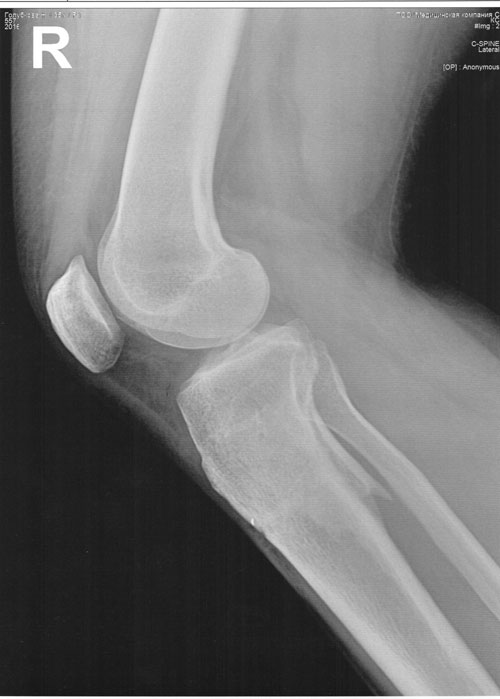

рентген в 60 дней.

Сращение идёт хорошо. Делаем рентген в 90 дней и готовимся к снятию.

рентген в 90 дней.

Отправляю вам контрольные рентген-снимки и фото ножек. Со дня снятия прошло 50 дней.

Здравствуйте, Наталья! По рентгену, всё отлично! разрешено всё без ограничений! Исключить: беременность в течении первых 6 месяцев.